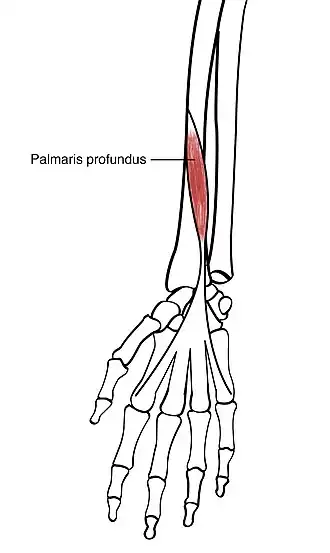

Palmaris profundus muscle

Palmaris profundus muscle originates from the lateral edge of radius and inserts to palmar aponeurosis. | |

Palmaris profundus (also known as musculus comitans nervi mediani[1] or palmaris bitendinous[2]) is a rare anatomical variant in the anterior compartment of forearm. It was first described in 1908.[3] It is usually found incidentally in cadaveric dissection or surgery.

Pirola et al.[4] classified the muscle into subtypes depending on its origin: (1) from the radius, (2) from the flexor digitorum superficialis fascia, and (3) from the ulna. Though, other origins of the muscle were reported including the medial epicondyle of humerus,[1] the palmaris longus[2] and the flexor pollicis longus.[5] It runs deep to the pronator teres and lateral to the flexor digitorum superficialis. Its tendon passes beneath the flexor retinaculum through the carpal tunnel before broadening out to insert to the deep part of palmar aponeurosis.

In many cases, the muscle is contained within the same fascial sheath as the median nerve. To indicate this association, the term musculus comitans nervi mediani is often used.[1] It can also be referred to as the palmaris bitendinosus when originating from the palmaris longus.[2] It can be considered a variation of the palmaris longus, however, it may exist in addition to the palmaris longus. If both of them coexist, the aberrant palmaris profundus tends to be the deeper one.[6]